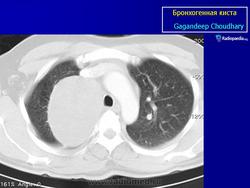

Рентгенологическая картина. При кисте, заполненной жидкостью, обнаруживается округлое или овальное затенение с четкими контурами. Контуры затенения могут изменяться в зависимости от фазы дыхания. При бронхогенной кисте, заполненной воздухом, видна правильной формы полость с чрезвычайно четким контуром, на фоне которой легочный рисунок обычно ослаблен. Более отчетливо просветление прослеживается на томограммах. Небольшой уровень жидкости на дне наблюдается не всегда, однако этот симптом, весьма важен с точки зрения дифференциальной диагностики истинных бронхогенных кист, продуцирующих секрет, от воздушных полостей другого происхождения (булл). Бронхография. Контраст не всегда попадает в полость из-за чрезвычайно узкого сообщения последней с просветом бронхиального дерева.

ID: 22985 Bronchogenic cyst Dr Mostafa Mahmoud El Feki - 10 May 2013 Features consistent of bronchogenic cyst. Differential considerations in...

ID: 10946 Bronchogenic cyst Dr Gagandeep Choudhary - 3 Oct 2010 CT through the chest demonstrates a large fluid density cystic structure...